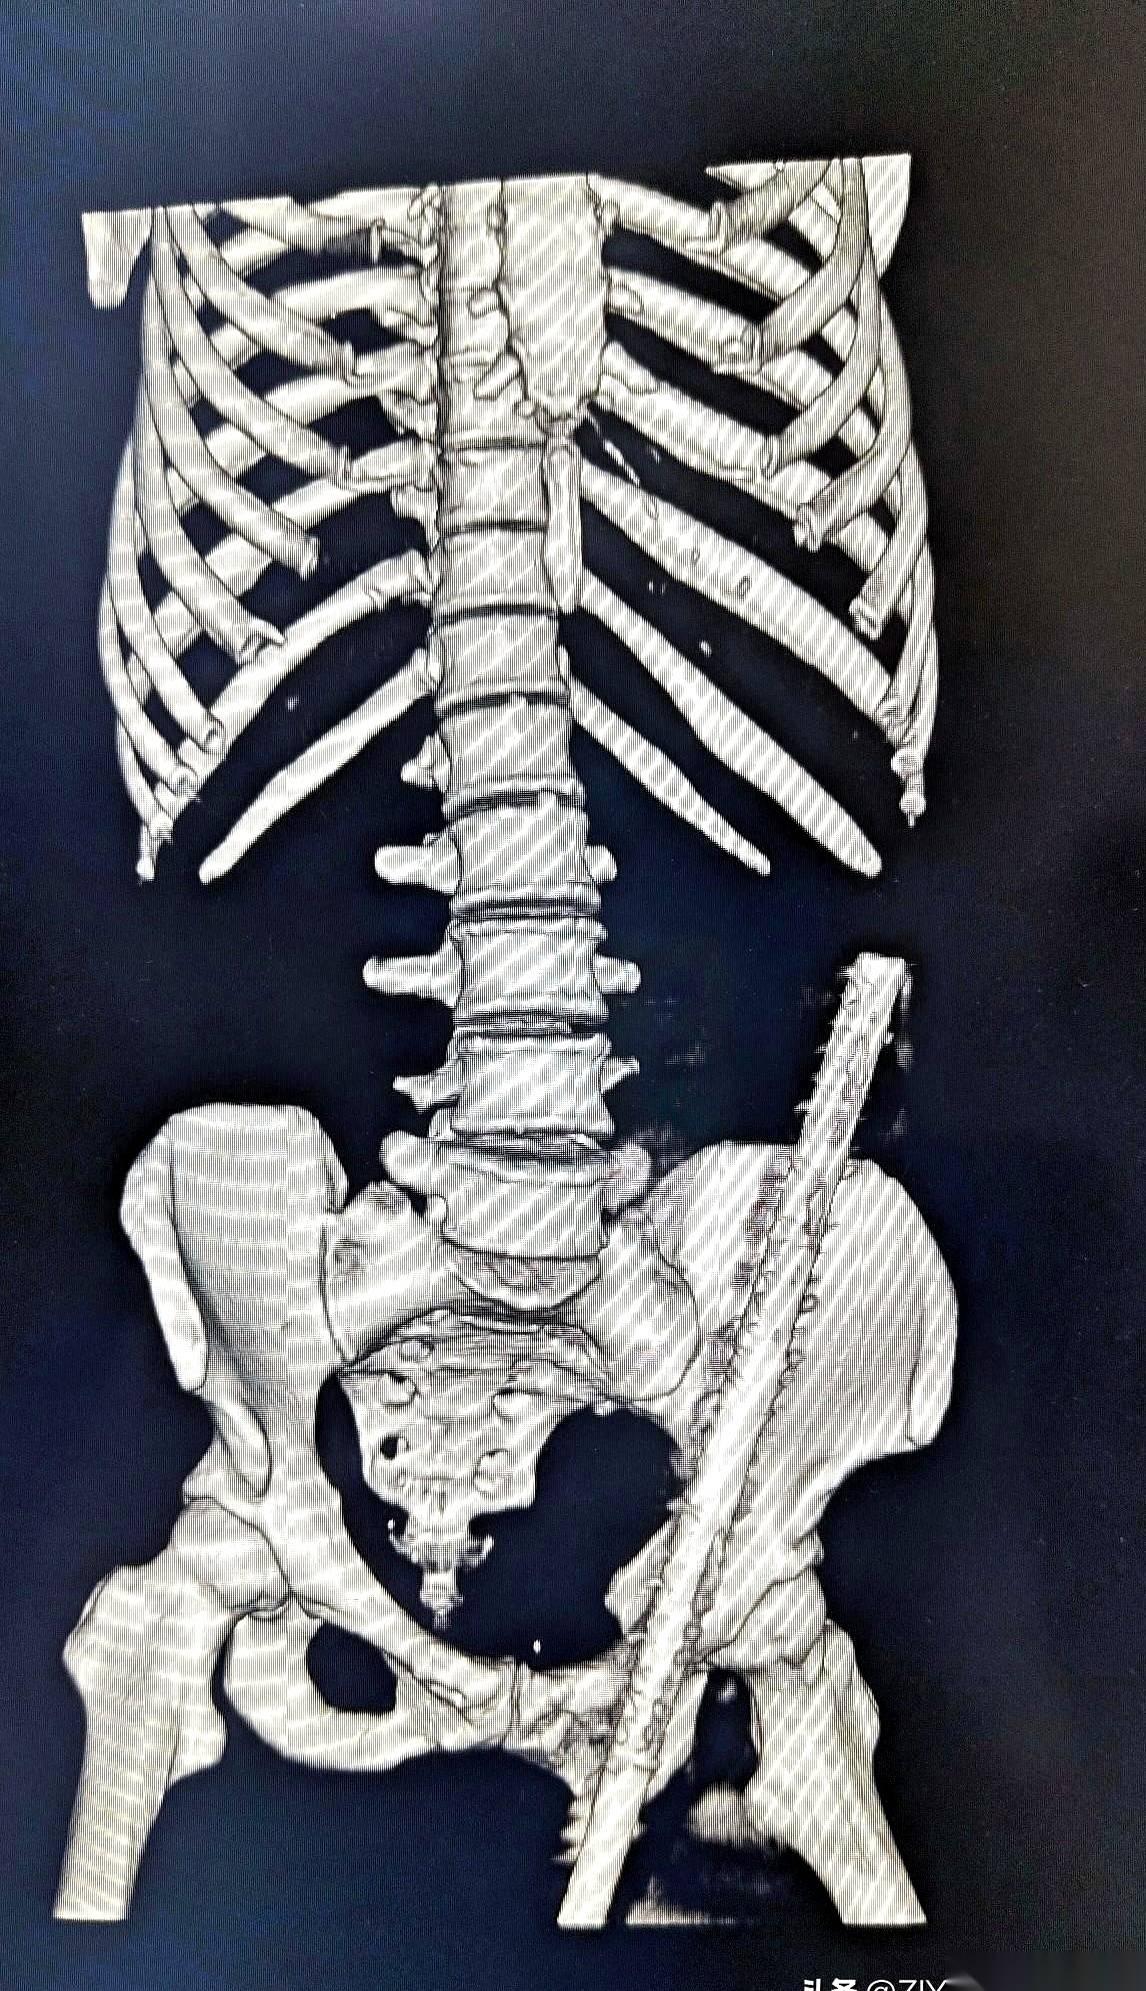

急诊室的门一推开,所有人的声音都小了下去。 担架上躺着一个女人,47岁,工地上干活的。一根粗钢筋,从她身体下方贯穿,从另一头的腹部皮肤顶了出来。人是清醒的,但脸上没有一丝血色,嘴唇抖得说不出话。 没人敢碰那根钢筋。谁都清楚,这玩意只要偏一毫米,里面就是肠子、大血管。现在拔,等于亲手送她走。 检查室里,气氛凝重得像块铁。医生们盯着CT机,等着那个最终的“判决书”。机器嗡嗡作响,屏幕上,一帧一帧的黑白影像缓缓生成。 所有人都凑了过去,死死盯着那条刺眼的金属白线。 它进去了。斜着向上。然后,就在快要碰到一堆要命的器官时,它拐了个弯,贴着内壁,硬生生从脂肪层里挤出了一条路,最后从肚皮下钻了出来。 就差那么一点点。 一名老医生摘下眼镜,反复擦了擦,又戴上,再看一遍。没错,钢筋完美地避开了所有脏器。那个救了她命的东西,是她厚厚的脂肪。 这层平时可能让她烦恼的脂肪,像个垫子,硬是把死神的刀给隔开了。 只能说,有时候,你身上最嫌弃的东西,恰恰是你的保命符。